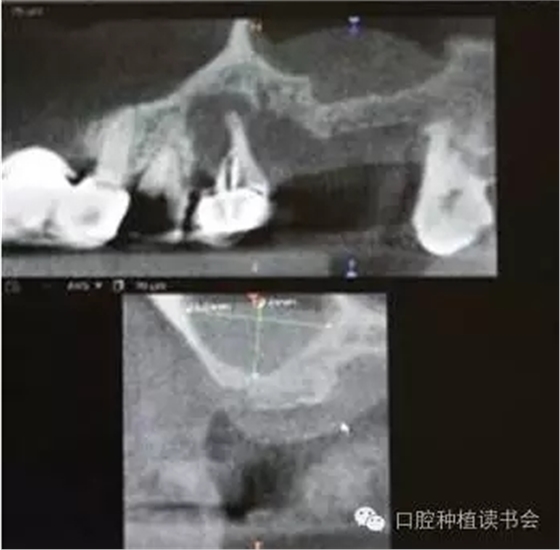

支配上頜竇的動(dòng)脈有上牙槽后動(dòng)脈(PSAA)、眶下動(dòng)脈和鼻后外側(cè)動(dòng)脈,手術(shù)時(shí)應(yīng)避免損傷。CBCT矢狀面可以觀察到上頜竇前外壁和后外壁的血管影像,PSAA從后外壁進(jìn)入上頜竇內(nèi),在冠狀面上則表現(xiàn)為位于骨壁外、骨壁內(nèi)或貫穿骨壁的血管影像(圖6-7)。

PSAA與眶下動(dòng)脈吻合,分布在上頜竇粘膜,常位于骨壁內(nèi)或貫穿骨壁。尸檢報(bào)告顯示,動(dòng)脈最低點(diǎn)距牙槽脊頂?shù)拇怪备叨染禐?1.25+2.99mm,距上頜竇底約8mm(Solar,1999)。因此,上頜竇提升時(shí),即使是非開(kāi)窗的牙槽脊頂入路,也有出血的風(fēng)險(xiǎn)(圖8-9)。